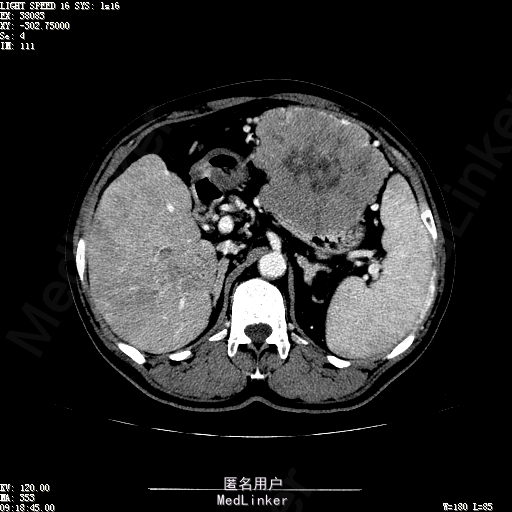

查体:生命体征平稳,神志清晰,发育正常,营养中等,体位自如,表情安静,无面容,配合检查合作。皮肤粘膜颜色正常,腹型平坦,无腹壁静脉曲张,未见胃肠型及蠕动波,无瘢痕,脐部正常。触诊:无压痛,无反跳痛,无腹肌紧张,无腹部包块。肝未触及,Murphy征阴性,脾未触及,肾未触及,无移动性浊音。 化验回报:血细胞分析(五分类):*白细胞计数 4.6 10^9/L、红细胞计数 4.27 10^12/L、血小板计数 100.0 10^9/L、血红蛋白 145 g/L、中性粒细胞百分比 68.6 %,*葡萄糖测定:葡萄糖 5.99 mmol/L,血清离子测定:*钾 4.46 mmol/L、钠 143.5 mmol/L,肾功能检测:*尿素 6.86 mmol/L、肌酐 84.2 umol/L,凝血五项:凝血酶原时间 10.7 秒、凝血酶原百分活动度 93.3 %,乙肝六项:乙型肝炎病毒表面抗原 阳性(+) 、乙型肝炎病毒e抗体 阳性(+) 、乙型肝炎病毒核心抗体 阳性(+) ,甲胎蛋白测定:甲胎蛋白 7146.00 ng/mL,ALT23U/L,AST42U/L CT检查如下图

诊断:乙肝肝硬化 静止性 代偿期 原发性肝癌 2型糖尿病 高血压病 下肢动脉闭塞征 诊断依据:1.有明确乙肝肝硬化病史 2.肝区隐痛,于外院发现肝占位,我院诊断肝癌,已行TACE治疗 3.查体:有肝掌 4.既往影像学提示肝内占位 处置:血管介入治疗:患者平卧位,以左侧肘窝为中心常规消毒、铺巾、利多卡因局麻。超声引导下,于肘横纹上方1厘米处确定皮肤穿刺点,改良Seldinger法逆行穿刺左侧肱动脉成功,置入5F血管鞘。沿导丝送入Cobra C2导管,送入降主动脉,将管头送入腹腔干,进一步送至肝固有动脉。造影见肝内广泛弥漫肿瘤染色,以右叶为主。以微导管超选肝右动脉,造影明确为肿瘤供血动脉,注入碘化油5毫升。退出微导管,经C2管注入奥沙利铂100毫克。退出C2管。拔出血管鞘,局部压迫10分钟。加压包扎。患者送返病房。